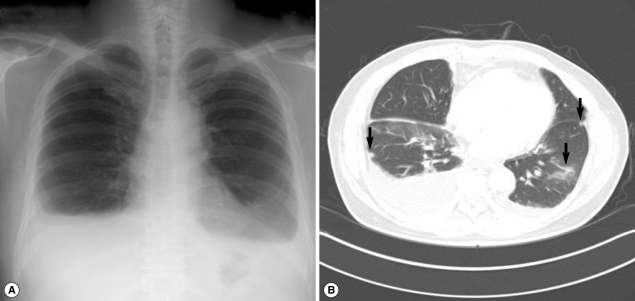

A 54-year-old man (the husband of case 1) visited our hospital to seek for treatment of sudden dyspnea accompanied by dry cough, 2 months after his wife had been treated for paragonimiasis. He had previously been healthy with no prior medical problems. However, his body weight decreased by 4 kg. He had eaten Kejang with her wife during the same period. On physical examination, his breathing sound was decreased in the lower lung zone. A CBC revealed WBC level of 21,800/mm3, hemoglobin level of 13.5 g/dl, platelet level of 258,000/mm3, and AEC of 13,580/mm3. Other laboratory tests revealed no abnormal findings. A simple chest x-ray revealed extensive pleural effusion in both hemithoraces (Fig. 2A). A chest CT also revealed extensive pleural effusion, as well as atelectasis and ground glass opacity in the lower lung and pleural nodules (Fig. 2B). According to the laboratory findings, image work-up, and recorded family history, stool examinations and ELISA tests were followed. As a result, Paragonimus eggs were observed in the stool sample, and ELISA test was positive for antibodies against Paragonimus westermani. The patient's total serum IgE level was 341 kU/L (cut-off level; below 100 kU/ml). On the basis of these findings, the patient was subsequently treated with praziquantel (25 mg/kg, 3 times daily for 2 days). The patient's symptoms of dyspnea were resolved after the treatment. A week after the medication, the patient's AEC decreased from 13,580/mm3 to 7,300/mm3, and an improvement in the left pleural effusion was observed.

Fig. 2

Simple chest x-ray and CT findings in case 2. (A) Extensive pleural effusion is seen in both hemithoraces. (B) Atelectasis, ground-glass opacity in the lower lung and a few subpleural nodules (arrow) are observed in both lungs (arrow).

Fig. 2 Simple chest x-ray and CT findings in case 2. (A) Extensive pleural effusion is seen in both hemithoraces. (B) Atelectasis, ground-glass opacity in the lower lung and a few subpleural nodules (arrow) are observed in both lungs (arrow).